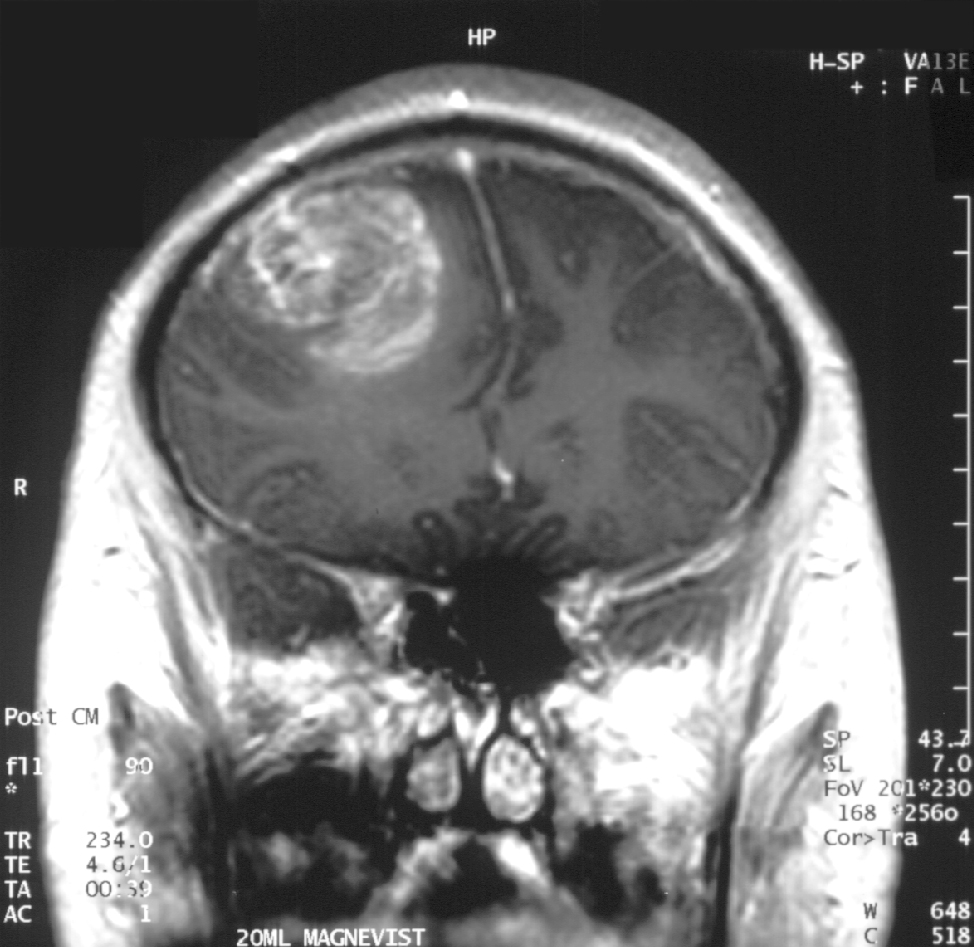

Glioblastoma ostaje jedan od najagresivnijih i najsmrtonosnijih oblika raka mozga, s medianom preživljavanja od samo 12–18 mjeseci nakon dijagnoze. Novu nadu donosi istraživanje australskih znanstvenika iz Centre for Cancer Biology (CCB) pri Sveučilištu Adelaide, koje je otkrilo nepoznatu ulogu CD47 proteina u poticanju rasta ovog tumora – nezavisno od njegove poznate uloge u izbjegavanju imunološkog odgovora. Studija objavljena u Proceedings of the National Academy of Sciences (PNAS) pokazala je da CD47 ne djeluje samo kao 'ne vidim me' signal za imuni sustav, već aktivno potiče proliferaciju stanica glioblastoma kroz međustanične signale. To je ključna promjena u razumijevanju mehanizma bolesti: dotad se CD47 smatrao isključivo imunološkim 'štitom', dok sada postaje direktna meta za usporavanje rasta tumora. Međutim, važno je istaknuti razinu dokaza: radi se o pretkliničkoj studiji na miševima, bez ljudskih kliničkih ispitivanja. Eksperimentalni modeli koriste genetički modificirane glodavce s ljudskim tumorima, ali prijenos rezultata na pacijente zahtijeva godine dodatnih istraživanja. Čak i ako se potvrdi, blokiranje CD47 neće biti 'čudo-lijek', već potencijalni dodatak postojećim terapijama kao što su kirurgija, radioterapija i temozolomid.

Što ovo značajno ne pokazuje? Prvo, studija ne dokazuje da će blokatori CD47 (poput već postojećih anti-CD47 antitijela) usporiti glioblastom kod ljudi. Drugo, nema podataka o nuspojavama dugoročne inhibicije CD47 – protein je prisutan i na zdravoj tkivu, pa njegov blok može imati nepredvidive posljedice. Treće, glioblastoma je heterogen tumor s više međusobno povezanih putova rasta; ciljanje samo CD47 vjerojatno neće biti dovoljno. Za pacijente danas ništa se ne mijenja. Trenutne smjernice Europskog društva za neuro-onkologiju i dalje se oslanjaju na standardne protokole, a CD47 inhibitori su još u ranim fazama kliničkih ispitivanja (npr. NCT03248479 za magrolimab). Što dalje? Potrebna su ispitivanja na ljudima s jasnim biomarkerima koji će identificirati podgrupe pacijenata koji bi mogli imati korist. Također, treba razumjeti dugoročne učinkovitost i otpornost tumora na ovu terapiju – problem koji je već dokumentiran kod drugih ciljanih lijekova. Znanstvena zajednica reagira oprezno. Dr. David Ashley, direktor Duke Centra za glioblastom, ističe da je 'ova studija važan korak, ali samo jedan od mnogih potrebnih'. Slično, Američko društvo za istraživanje raka (ACS) u svojim smjernicama naglašava da 'pretklinički rezultati rijetko se direktno prevedu u kliničku praksu' – upravo zato što ljudski organizam nije laboratorijski model.